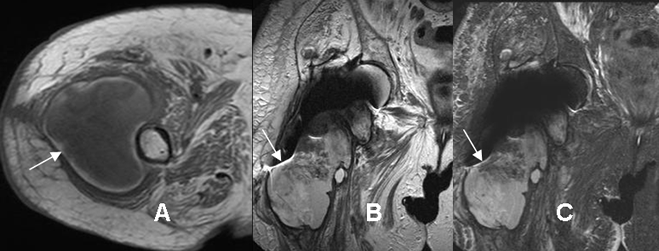

Fig 23. Miositis.

A: RM axial en T1 y B: RM axial en STIR. Cambios inflamatorios en los músculos pectíneo y obturador externo, los cuales son hipointensos en T1, hiperintensos en STIR y rodeados por líquido, por miosistis. Hay prótesis en la cadera, que produce artefactos.

Fig 24. Absceso.

A: RM axial en T1, B: RM coronal en T2 y C: RM coronal en STIR. Igual paciente anterior. Se encuentra gran colección en la parte lateral del fémur, de bordes bien definidos y señal heterogénea e intermedia en T1, hiperintensa en T2 y STIR, que corresponde a absceso. Prótesis metálica en la cabeza femoral, que produce artefactos.